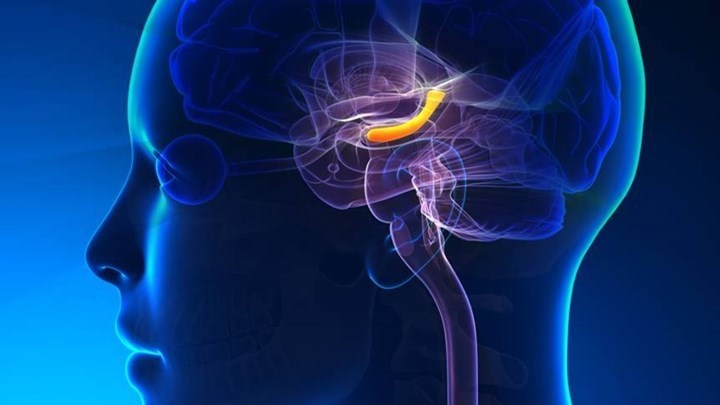

Υπάρχει αρσενικός και θηλυκός εγκέφαλος; Ένας εγκέφαλος αποκομμένος από το σώμα είναι ο ίδιος εγκέφαλος;

“Προφανώς υπάρχει αρσενικός και θηλυκός εγκέφαλος, διότι γεννιόμαστε με αρσενικό και θηλυκό εγκέφαλο. Υπάρχει σαφέστατη διαφορά ανάμεσα στους άντρες και τις γυναίκες, διότι όταν βρισκόμαστε μέσα στη μήτρα, κάτω από την επίδραση συγκεκριμένων ορμονών, όπως είναι η τεστοστερόνη ή όπως είναι η οιστραδιόλη, ο εγκέφαλος γίνεται αρσενικός ή θηλυκός. Αυτό δείχνει ποιες είναι οι ιδιαιτερότητες του φύλου μας. Ανατομικά βέβαια υπάρχουν κάποιες διαφορές. Ποτέ όμως δεν ήταν πολύ ξεκάθαρο αν οι ανατομικές αυτές διαφορές είναι εκείνες, οι οποίες οδηγούν και σε διαφορά στη συμπεριφορά μας ή αν οι περισσότερες διαφορές μας είναι προϊόντα κοινωνικοποίησης και ορισμένων τάσεων, που υπάρχουν στην κοινωνία, οι οποίες οδηγούν τα κορίτσια να συμπεριφέρονται με ένα τρόπο και τα αγόρια με κάποιον άλλον” εξηγεί στο ΑΠΕ ο καθηγητής του Τμήματος Κτηνιατρικής του ΑΠΘ, Θανάση Ντινόπουλος.

Στο ερώτημα “αν ένας εγκέφαλος αποκομμένος από το σώμα είναι ο ίδιος εγκέφαλος” ο κ. Ντινόπουλος απαντά αρνητικά. “Ο εγκέφαλος είναι κατά κάποιο τρόπο κλεισμένος μέσα σε ένα σκοτεινό κουτί και έρχεται σε επαφή με το σώμα μας και το περιβάλλον. Η τροφοδότηση από το σώμα μας και από το περιβάλλον είναι αυτά που κάνουν τον εγκέφαλο τελικά να είναι αυτό που είναι. Βέβαια ο εγκέφαλος παίζει καθοριστικό ρόλο, γιατί συντονίζει όλες αυτές τις πληροφορίες και μας οδηγεί σε αποκρίσεις, σε συμπεριφορές και σε συναισθήματα, αλλά αποκομμένος δεν θα ήταν ποτέ ο ίδιος εγκέφαλος. Δηλαδή, αν πάρουμε έναν εγκέφαλο, τον βάλουμε μέσα σε μία γυάλα με οξυγόνο και τον διατηρήσουμε σε λειτουργία, δεν θα είναι ο ίδιος εγκέφαλος, διότι ακριβώς δεν έχει τις πληροφορίες από το σώμα και το περιβάλλον, ώστε να μπορέσει να δράσει ως πραγματικός εγκέφαλος” προσθέτει ο κ.Ντινόπουλος.